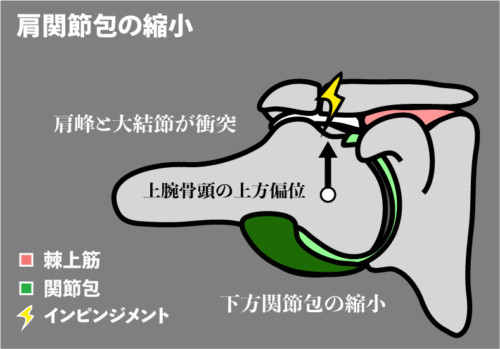

下方関節包の縮小(肩関節周囲炎など):骨頭が潜り込めず上方へ押し出され衝突。

② 肩関節拘縮(関節包の縮小)

機序

後方~下方関節包が短縮→骨頭が潜れず最終挙上で伸張痛。